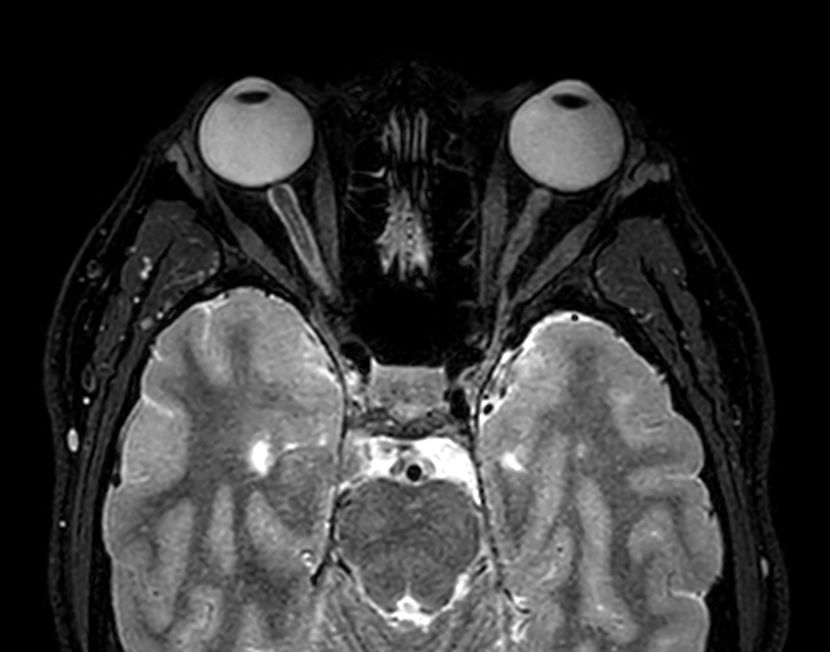

Axial 3D VIEW - T2w FatSat

-